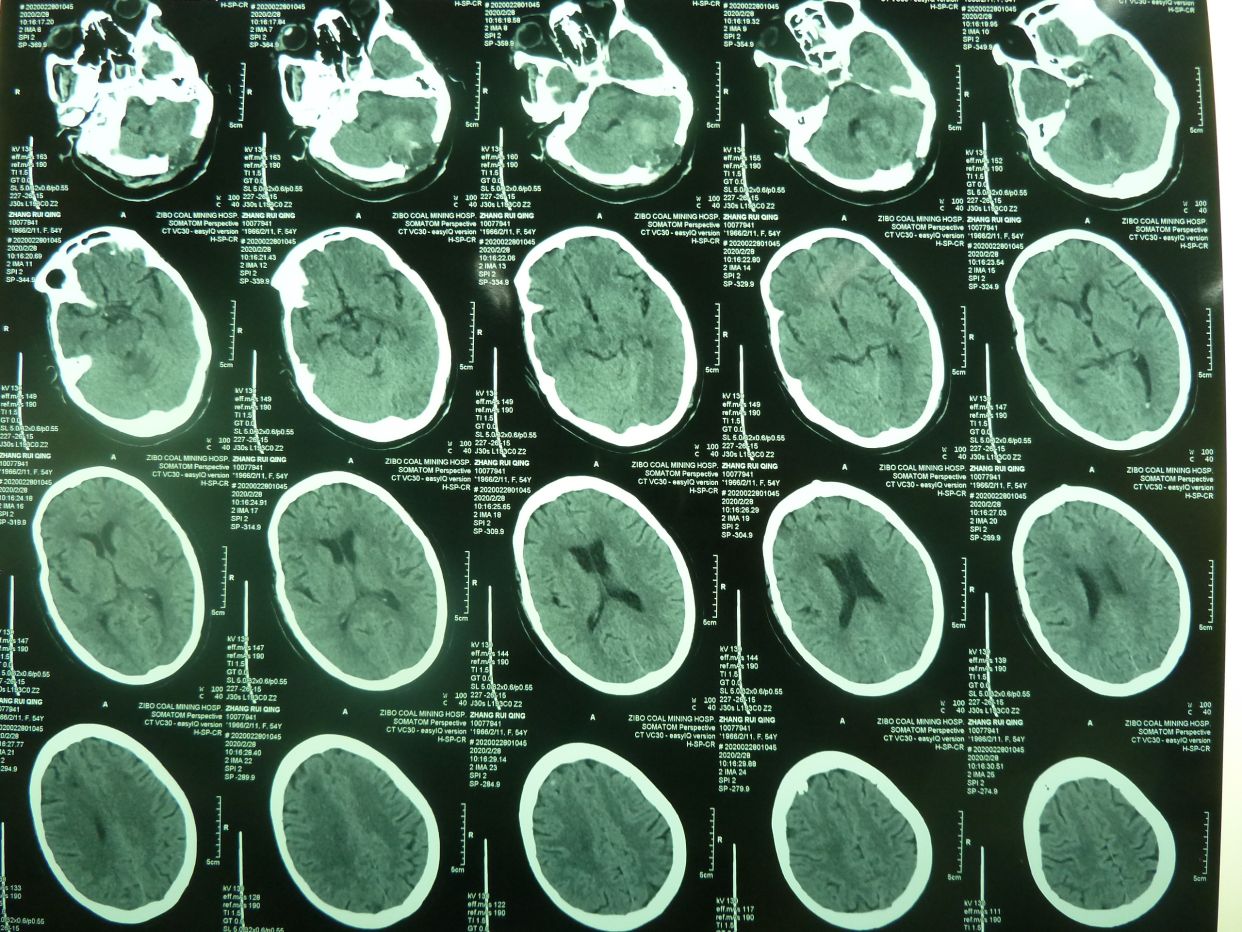

CT显示小脑大量出血并破入全脑室,梗阻性脑积水,脑干受压变形,与家属沟通并签字后,急症行脑室引流术,后颅凹开颅血肿清除术,气管切开术。

术后3天CT复查示,血肿清除满意,基底池四脑室可见。

术后四周CT复查,脑沟回清楚,无脑积水征象,患者神志清,四肢可遵嘱动作,出院康复。